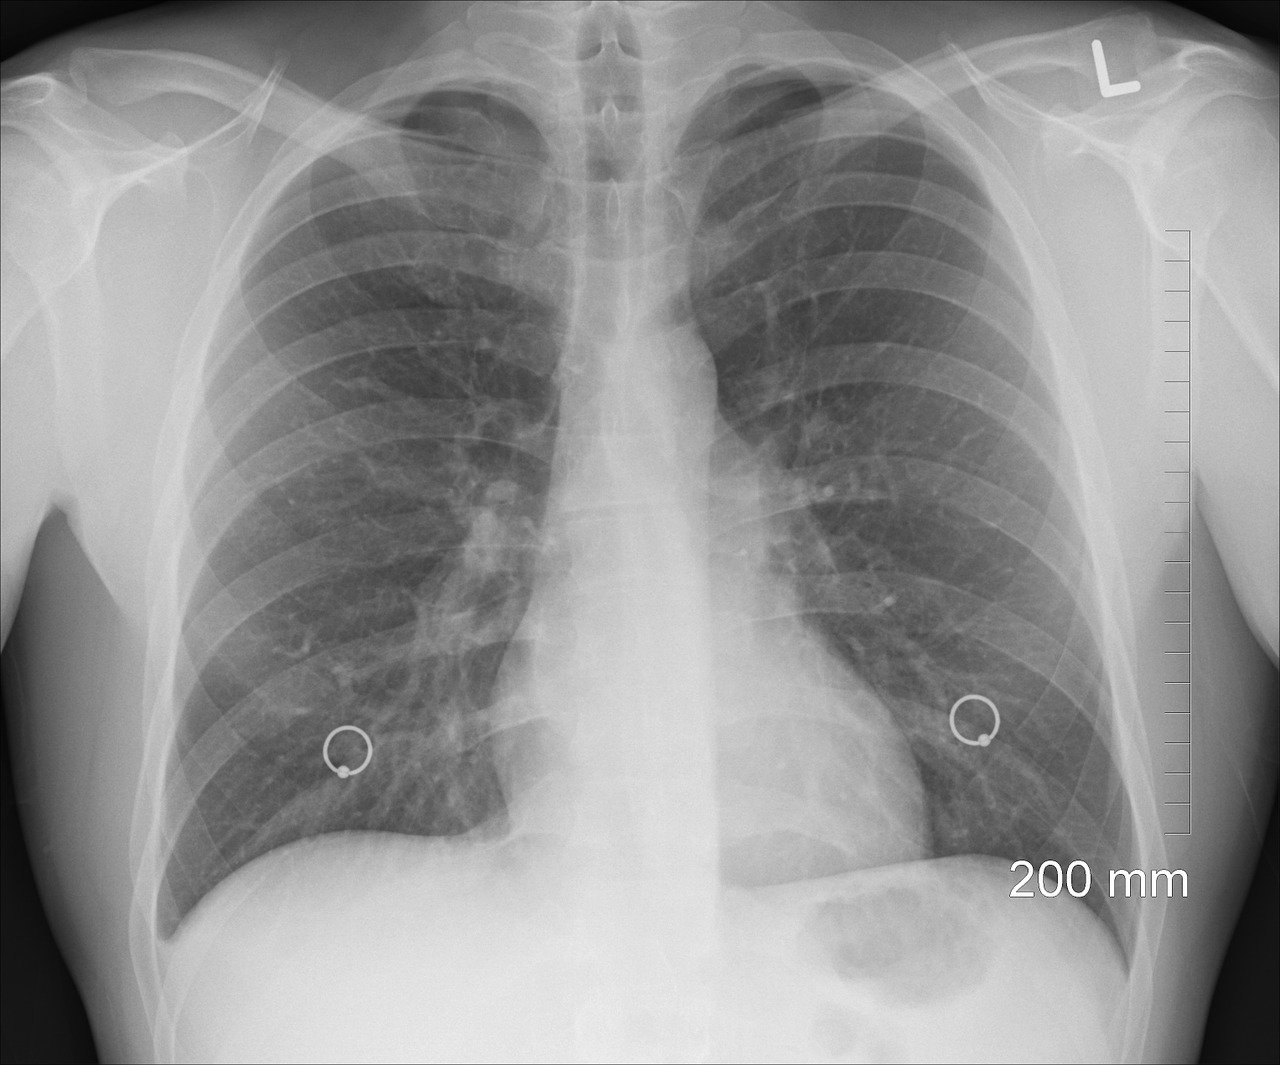

Laut Experten vom Dienstag erhalten in Ungarn insgesamt 300.000 Asthmapatienten medizinische Versorgung und schätzungsweise 150.000 leben mit dieser Erkrankung.

Bei insgesamt 15.000-20.000 Patienten wird in Ungarn jedes Jahr Asthma diagnostiziert und 15.000-30.000 leben mit chronischem Asthma

Lilla Tamási, Lungenärztin an der Budapester Semmelweis-Universität, sagte am Weltasthmatag und fügte hinzu, dass chronisch Erkrankte fortgeschrittene Behandlungen erhalten.

Ein großes Problem sei, dass rund 50 Prozent der Asthmapatienten ihre Medikamente nicht regelmäßig einnehmen, 90 Prozent davon würden von der nationalen Krankenkasse bezahlt, sagte Tamási, stellvertretender Direktor der Pneumologischen Klinik der Universität.